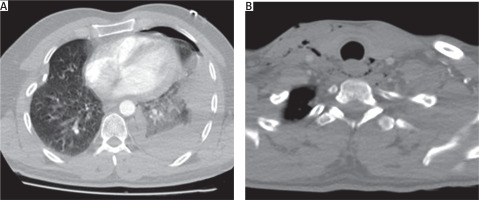

Contrast-enhanced computed tomography (CT) of the neck and thorax revealed a left-sided hydropneumothorax, an unexpected finding given the right-sided cervical entry point of the stab wound. Careful evaluation of the CT images demonstrated a linear tract of mediastinal emphysema extending posterior to the esophagus, suggesting that the penetrating object had followed a retroesophageal path (Figures 1 A, B). An urgent left-sided tube thoracostomy was performed, and the patient was admitted to the intensive care unit for close monitoring. Initial drainage was hemorrhagic in character, totaling approximately 700 ml within the first 24 hours. Given the left-sided vascular findings and the retroesophageal air tract noted on CT, there was a clinical concern for possible concomitant esophageal or tracheal injury. To minimize the risk of contamination in the event of an esophageal perforation, oral intake was withheld. On the first post-admission day, both bronchoscopy and upper gastrointestinal endoscopy were performed, and no evidence of tracheal or esophageal injury was identified.

Figure 1

Computed tomograpohy (CT) images demonstrating the unusual trajectory of a contralateral penetrating cervical injury. A – Axial thoracic CT showing a left-sided hydropneumothorax and lung contusion. B – Axial cervical CT revealing retroesophageal air tracking indicative of mediastinal penetration